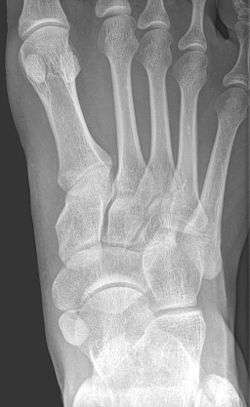

Accessory navicular bone

An accessory navicular bone is an accessory bone of the foot that occasionally develops abnormally in front of the ankle towards the inside of the foot. This bone may be present in approximately 2-21% of the general population and is usually asymptomatic.[1][2][3][4] When it is symptomatic, surgery may be necessary.